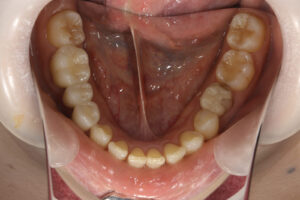

ラミネートベニア・セラミックインレー・アンレー・クラウン

内: セラミックインレー1本/80,000円、 セラミックアンレー80,000円、

ラミネートベニア1本120.000円

クリーニングの後、上顎前歯2本のラミネートベニア、右下臼歯部にセラミックブリッジを装着した。